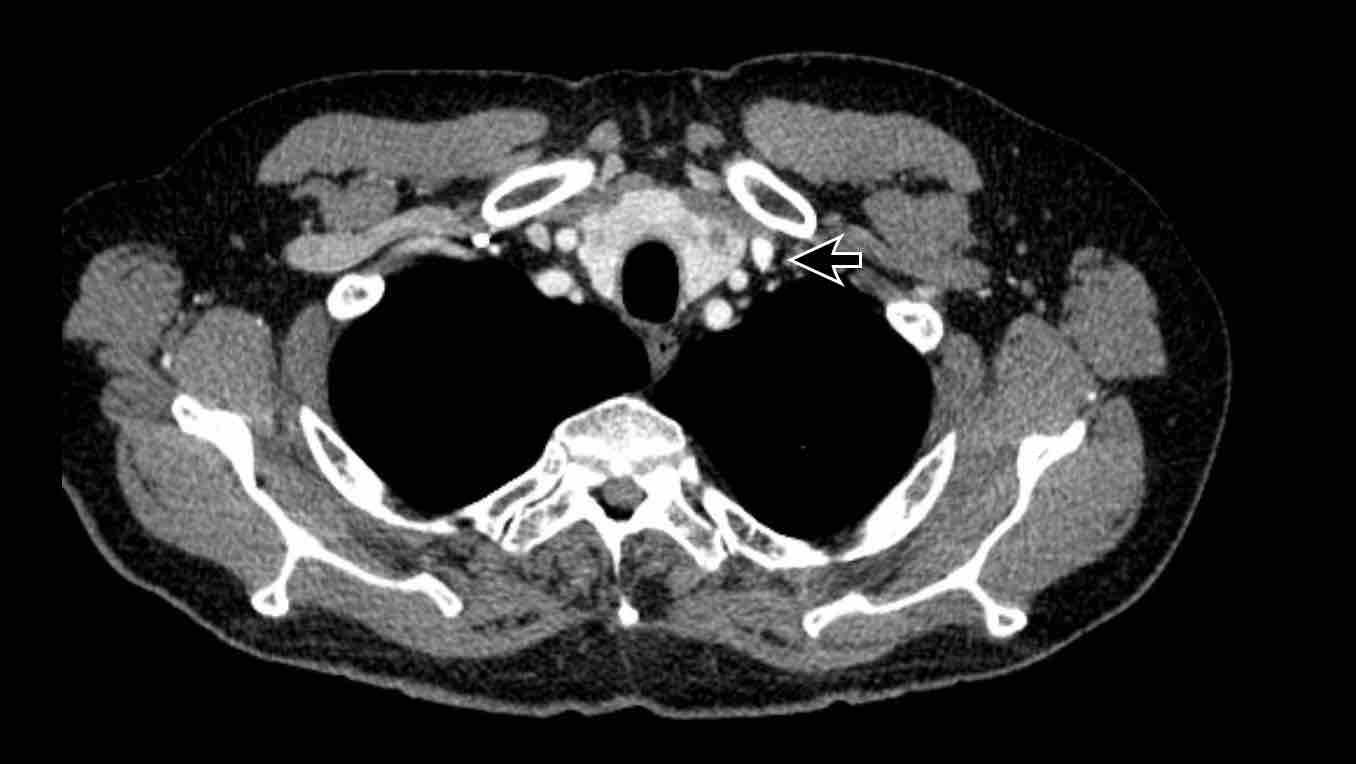

Tĩnh mạch liên sườn trên trái – Dấu hiệu “núm vú động mạch chủ”

Tĩnh mạch liên sườn trên trái là một cấu trúc có thể bắt chước các biến thể mạch máu ở phía bên ngoài cung động mạch chủ.

Đây là một cấu trúc tĩnh mạch bình thường được xem là một phần của hệ thống bán tĩnh mạch đơn, đôi khi nổi bật hơn ở một số người tùy thuộc vào lưu lượng tuần hoàn bàng hệ.

Do vị trí của nó, cấu trúc này có thể gợi ý bất thường hồi lưu tĩnh mạch phổi, tĩnh mạch chủ trên trái hoặc tĩnh mạch hồng y nhĩ trái; tuy nhiên, việc đánh giá nguyên ủy và đường đi của cấu trúc mạch máu sẽ giúp phân biệt cấu trúc tĩnh mạch bình thường này với các chẩn đoán phân biệt về bất thường mạch máu nêu trên.

Hình ảnh

Tĩnh mạch liên sườn trên trái nổi bật, đôi khi được gọi là ‘núm vú động mạch chủ’.

Lưu ý sự tương đồng với tĩnh mạch hồng y nhĩ trái (trên mặt cắt ngang).